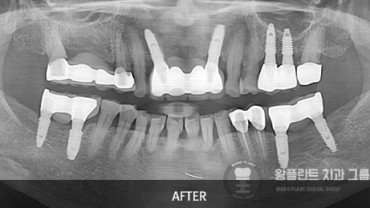

치료전후 사례

왕플란트 청량리점의 풍부한 경험과 기술력!

시술케이스를 통해 미리 확인해보세요 !